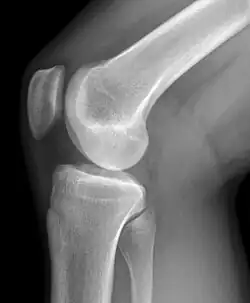

Radiographie d'un genou

Il existe différentes modalités d'imagerie pour explorer la pathologie du genou. La radiographie, souvent réalisée en première intention permet d'examiner l'état des cartilages, les détachements osseux et d'éventuels bâillements en position de schuss (flexion légère). La goniométrie consiste en la réalisation d'une radiographie de l'ensemble de la jambe pour observer les déviations du genou.